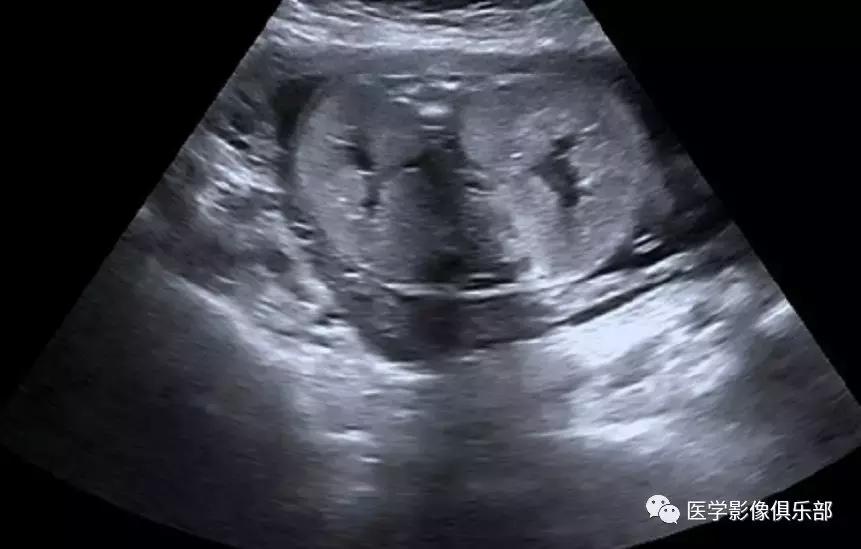

[典型病例二]:45岁,女性患者,腹部不适。家族史是动脉瘤性蛛网膜下腔出血和肾损害。

CTMPR冠状位重建显示双侧肾脏体积明显增大,肾脏皮质及髓质分界不清,弥漫大小不等的囊肿,边界光滑锐利,肝脏实质内亦可见多发大小不等的囊肿。